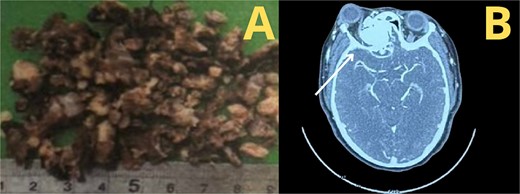

According to the information gathered, the surgeon decided to perform a partial resection of the maxillary neoplasia (Fig. 2). The chosen approach upon evaluation was the Caldwell–Luc procedure, gaining access to the maxillary sinus. Dimensions and anatomic relationships of the mass were established, determining an extension up to the sphenoid bone covering the ipsilateral choana. A predominantly osseous tumor was observed, with a significant contribution of trabecular bone, vascularized, exhibiting a tendency to hemorrhage. Partial resection of the tumor was accomplished, leading to visualization of the peripheral orbit but not decompressing it totally due to hemodynamic instability during intervention. A residual mass was left at the sphenoidal level and cranial base, a future reintervention was considered.

A second intervention was performed with the Caldwell–Luc approach for complete tumor removal.